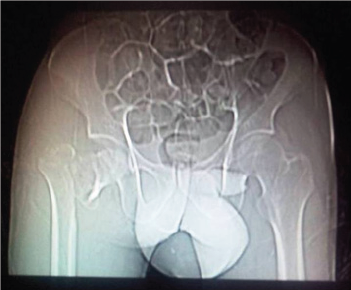

A 52 year old migratory laborer had an accident at civil construction site where he fell down from a height of 20 feet landing first on knees (in kneeling position). He presented to emergency department with severe pain in right groin, and inability to move the left lower limb. On examination the limb was shortened, externally rotated and a bony mass felt in the loin which did not move with the movement of distal thigh. There was severe tingling and decreased sensation in front and lateral aspect of leg and patient was unable to dorsiflex his ankle and toes. His pulsations were normal but he had had transient hypotension with tachycardia which corrected with initial resuscitation. First X ray showed fracture about right hip (Figure 1) mostly a trochanteric fracture but a careful evaluation showed incongruity of head and a "vacant" on super lateral acetabulum. A CT scan was followed wherein the fracture was better delineated. A posterior dislocation of hip with fracture about the trochanter was seen. The head was also fractured and the infra foveal part could be seen lying the acetabulum. A fracture line also ran through the posterior wall of acetabulum which was not more than 25% of the wall and also was undisplaced (Figure 2a- 2c). The patient was admitted and limb placed in Thomas splint and prepared for next morning. No attempts to reduce the dislocation were made.

Figure 1.